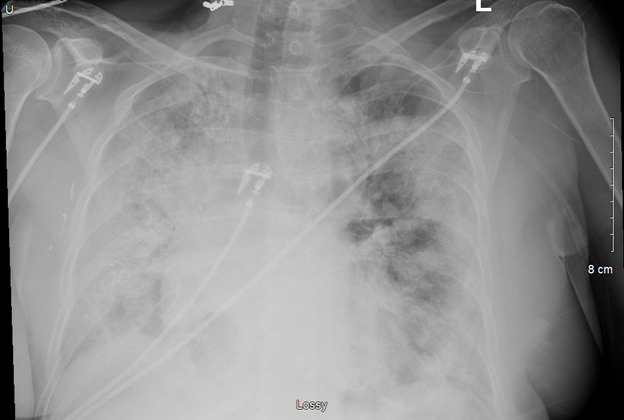

A 66-year-old female with no significant past medical history presented to the emergency department (ED) with a chief complaint of shortness of breath. She presented after approximately one week of symptoms with malaise, fatigue, and cough. On examination, she appeared anxious and in moderate distress with a respiratory rate of 39 breaths per minute (bpm) and pulse oxygen saturation (SpO2) of 81% on room air. She was placed on bilevel positive airway pressure (BiPAP). Laboratory tests were significant for a positive COVID-19 polymerase-chain-reaction (PCR) and elevated lactic acid (2.4 mg/dL) and inflammatory markers: ferritin (929.3 ng/mL), CRP (11.20 mcg/mL), and d-dimer (4.49 mcg/mL). Arterial blood gas (ABG) values following initiation of BIPAP were: pH 7.44, PaCO2 40 mmHg, PaO2 72 mmHg, O2 Saturation 95.1% on 100% FiO2. Chest Xray showed bilateral diffuse infiltrates consistent with acute respiratory distress syndrome.

She was admitted to the intensive care unit (ICU) with a working diagnosis of acute hypoxic respiratory failure secondary to COVID-19 pneumonia and likely superimposed bacterial infection. She was initiated on conventional therapies for COVID-19 at the time with dexamethasone 6 mg intravenously (IV) daily for 10 days and two doses of tocilizumab 8 mg/kg IV. Azithromycin and ceftriaxone were added empirically for suspected superimposed bacterial pneumonia. (Image 1) Blood and urine cultures were collected and eventually resulted in no microbial growth. Within 24 hours, the patient required intubation and mechanical ventilation for acute respiratory distress syndrome (ARDS).